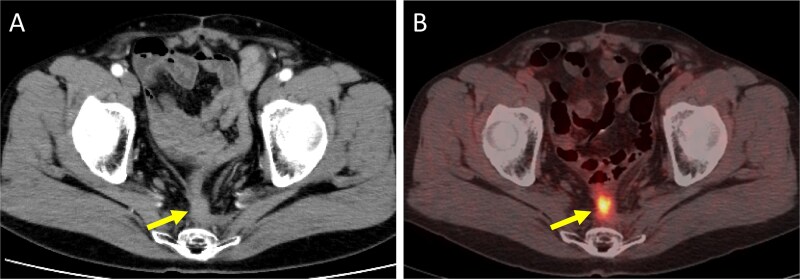

Treatment of locally recurrent rectal cancer (LRRC) after surgery is often complex and challenging. A 52-year-old man received emergency surgery (Hartmann's procedure) for bowel perforation caused by a huge sigmoid colon cancer, followed by treatment for concurrent advanced lower rectal cancer with neoadjuvant chemoradiotherapy and abdominoperineal resection. A solitary lung metastasis emerged afterwards, and was surgically removed. However, the patient developed LRRC in front of the sacrum. As surgical resection for the local recurrence was considered too invasive, carbon-ion radiotherapy (CIRT) was performed as radical local therapy. Because the surrounding intestine was highly adherent to the tumor and there was a high risk of developing an ulcer, the intestine was prophylactically resected. The patient has remained relapse-free for 2 years and 6 months since the most recent surgery. CIRT for LRRC appears to represent a useful therapeutic option in combination with prophylactic intestinal resection.